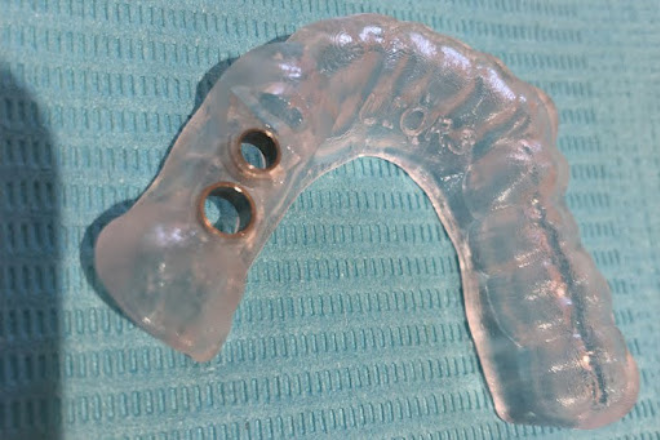

また、正確な埋入位置を導くサージカルガイドの導入も重要なポイントです。

2.検査結果をもとに治療計画を立案し、正確な埋入を実現するサージカルガイドを作製する段階です。